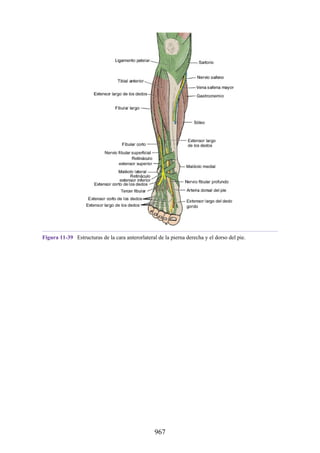

Notas clínicas

Lesiones ligamentosas